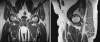

FIG. 2. A coronal T 1 -weighted magnetic resonance image of both hips (left) shows diffiuse low signal intensity throughout the left femoral head and neck. A corresponding coronal T 2 -weighted image with fat saturation (right) shows diffuse high signal intensity in the left femoral head and neck with a joint effusion. These findings are typical of transient osteoporosis of the left hip.